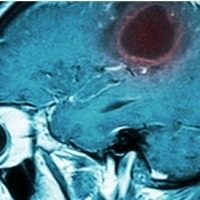

Kiedy w wieku sześciu lat u Lucasa zdiagnozowano rzadki rodzaj guza mózgu, rodzice przygotowywali się na najgorsze. Gdy większość znanych metod leczenia zawiodła, nieoczekiwany zwrot nastąpił po zastosowaniu eksperymentalnej terapii. 13-latek odzyskał zdrowie, a w jego głowie nie ma śladu po nowotworze.

Historia, którą opisuje serwis sciencealert.com, wydarzyła się w Belgii. Dokładnie 7 lat temu u Lucasa wykryto glejaka mózgu.

. Rozlany naciekający glejak mostu (DIPG, tzw.guz pnia mózgu) co roku dotyka około 300 dzieci w USA. Mimo że 85 proc. małych pacjentów przeżywa 5 lat od diagnozy, ogólne rokowania są bardzo złe. W leczeniu stosuje się m.in. radioterapię, która spowalnia rozrost guza, jednak do tej pory nie istniał żaden skuteczny lek. To może się niedługo zmienić, co udowadnia historia 13-letniego dziś Lucasa. Chłopiec zakwalifikował się do programu zajmującego się nowotworami centrum Gustave Roussy w Paryżu, aby jako jeden z pierwszych pacjentów dołączyć do badania BIOMEDE, w ramach którego testowane są potencjalne nowe leki na DIPG. Przełomowa terapia pomoże innym dzieciom?

Lucasowi podano lek o nazwie ewerolimus, na który od początku zareagował bardzo silnie. Guz po prostu zaczął znikać. Jak przyznaje lekarz prowadzący, Jacques Grill, patrząc na wyniki rezonansu magnetycznego aż trudno było uwierzyć, że guz z każdym tygodniem staje się mniejszy. Mimo pozytywnych efektów leczenia, lekarze podawali chłopcu lek jeszcze przez długi czas, zanim ostatecznie zakończyli terapię. Niestety, nie wiadomo jeszcze, dlaczego ten konkretny lek pomógł chłopcu i jak inni pacjenci zareagowaliby na taką samą terapię.

– Guz Lucasa miał niezwykle rzadką mutację, która naszym zdaniem spowodowała, że jego komórki były znacznie bardziej wrażliwe na lek – wyjaśniają lekarze.

Medycy ostrzegają jednak przed nadmiernym entuzjazmem: zanim lek zostanie dopuszczony do powszechnego użytku, zazwyczaj mija kilkanaście lat.